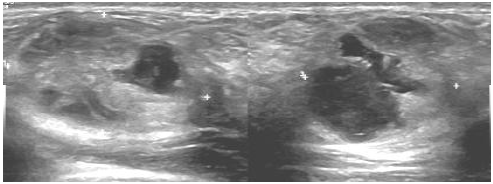

Paciente puérpera com 33 anos, informa que há duas semanas, durante amamentação, palpou um nódulo na mama direita.

O achado encontrado no exame de imagem classifica-se como: